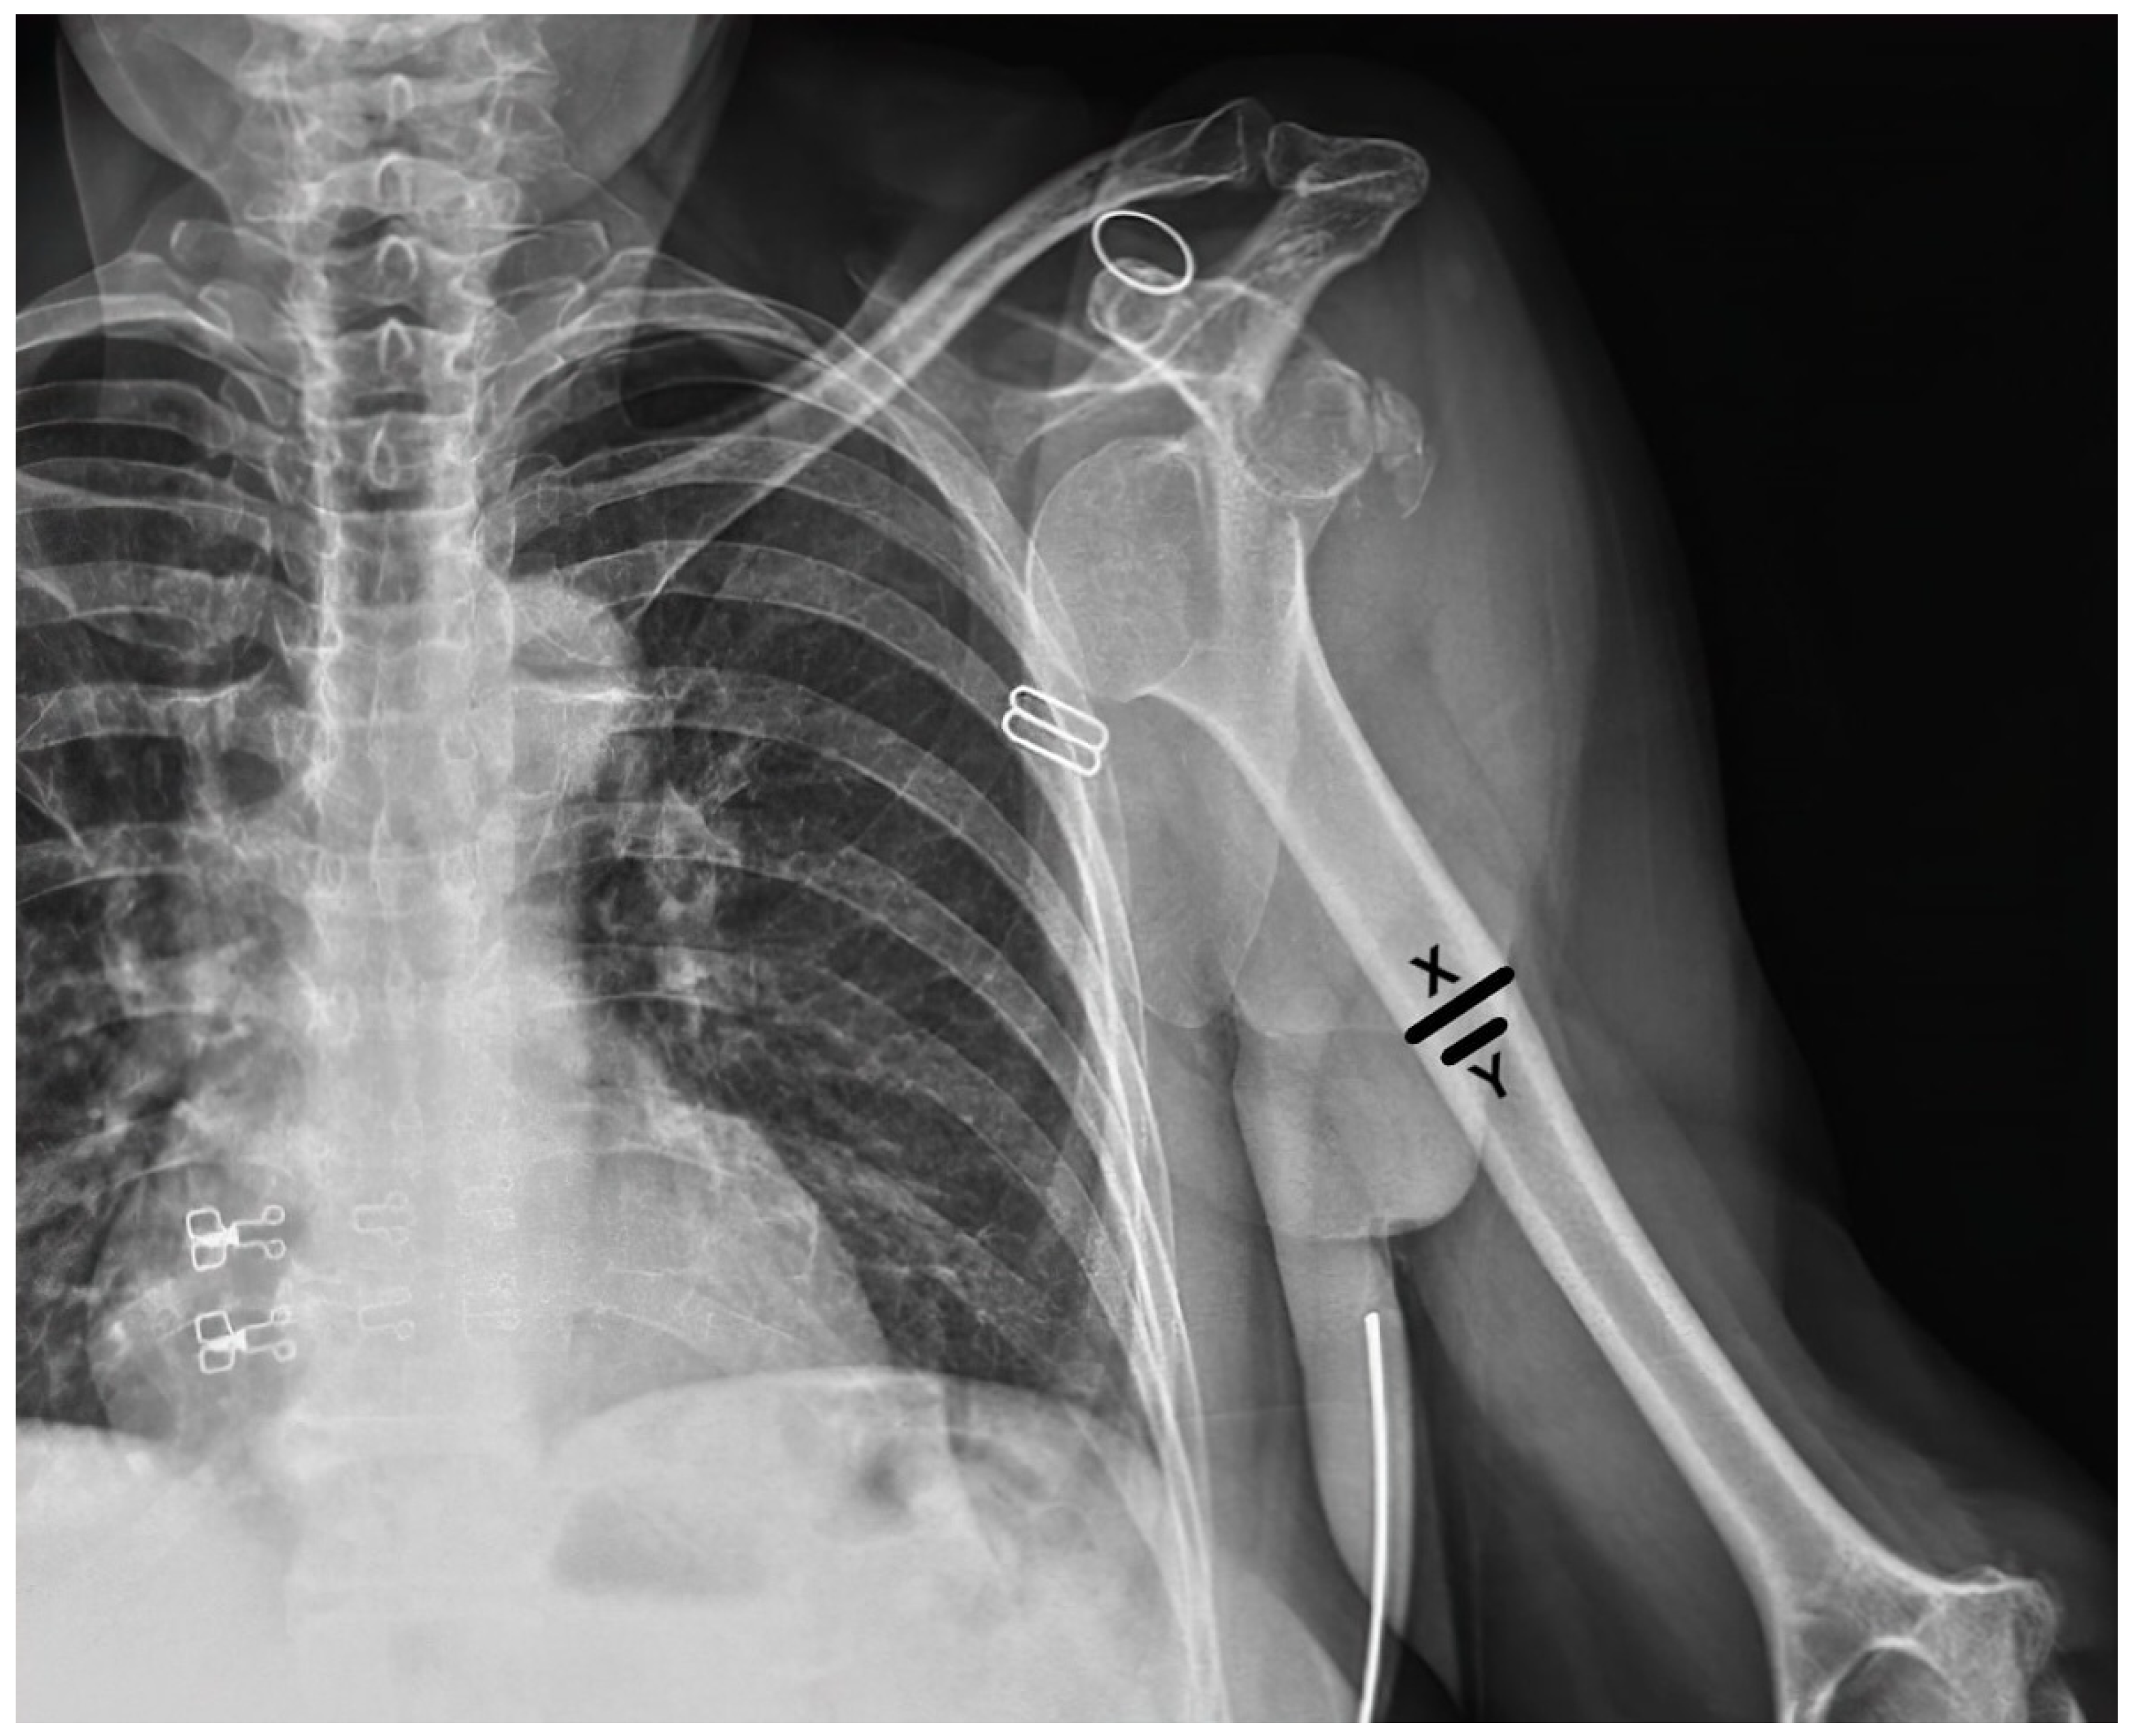

Demographic data such as age and gender were collected from the patient records. Dislocation directions, accompanying fractures, and post-reduction IHF were recorded. The traction–counter traction method was used in all reduction attempts, and the success of the reduction and the presence of preexisting GT fractures were also documented. Also, the deltoid tuberosity index [8] was measured to assess local bone quality (Figure 1). The traction-–counter traction method was used for all reduction attempts under conscious sedation. All reduction maneuvers were performed either by an orthopedic specialist or a resident under the supervision of a specialist. The experience level of the practitioner was not specifically analyzed in this study, as all procedures were conducted under standardized conditions to minimize variability in technique. For sedation, a midazolam–fentanyl combination was administered, with midazolam dosed at 0.05–0.1 mg/kg and fentanyl at 1–2 μg/kg. In cases where this combination was contraindicated, alternative sedative agents such as propofol or ketamine were used, based on the patient’s medical history and clinical condition. Anesthesia was applied to all of the patients to ensure muscle relaxation during the reduction process. Patients were divided into three groups, as follows: Group 1 included patients who had iatrogenic fractures during CR, regardless of the success of the reduction; Group 2 included those with failed CR attempts without IHF; and Group 3 included patients with successful reduction without IHF. In cases where both iatrogenic fractures and failed reduction occurred, patients were classified under Group 1 due to the presence of a fracture, as it represents a more significant complication. Unsuccessful reduction attempts and patients with iatrogenic surgical neck fractures were classified together as complicated reductions (Groups 1 and 2). In contrast, patients who had received successful CR with or without previous tuberculum majus fractures were classified as having “uncomplicated dislocations” (i.e., Group 3).

Figure 1. Measurement of the deltoid tuberosity index (DTI). The DTI is calculated by measuring the transverse diameter of the deltoid tuberosity at its widest point (X) and dividing by the narrowest transverse diameter (Y) of the humeral shaft at the same level.